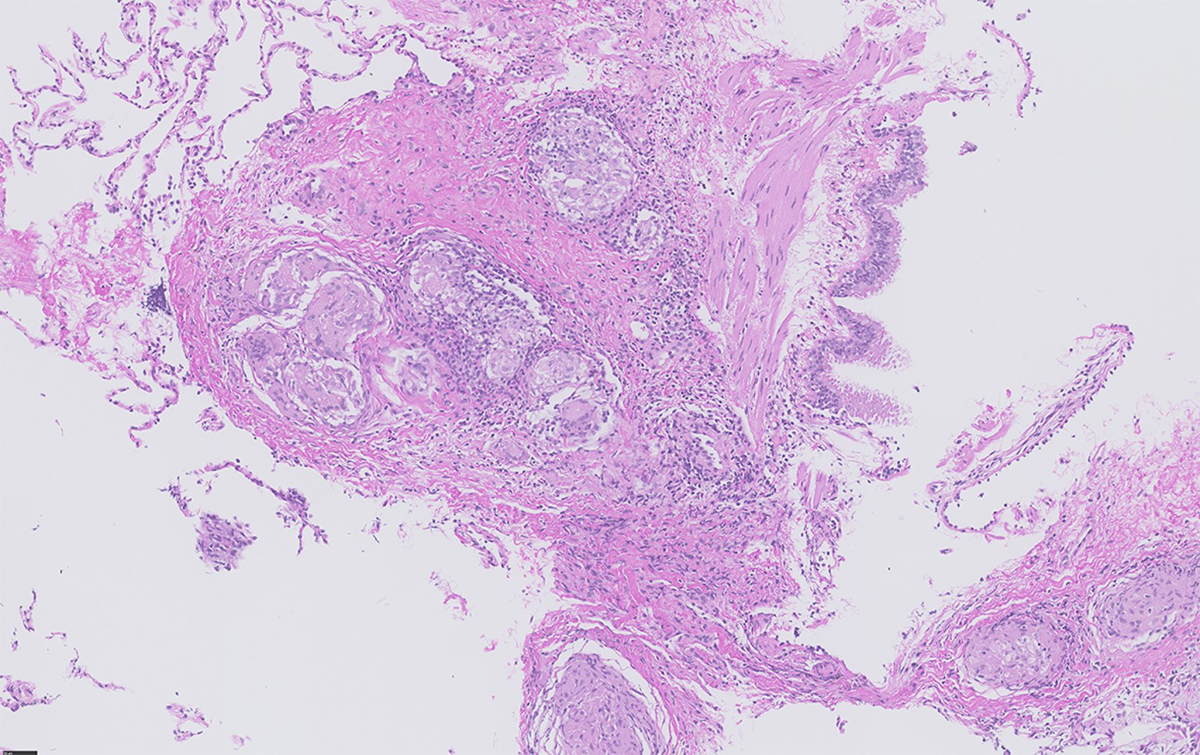

Epithelioid non-necrotising granulomas (fig. 1) represent the pathological hallmark of sarcoidosis with an innate immune response characterised by activated macrophages (transforming into epithelioid cells fusing into giant cells) and dendritic cells. This fosters an adaptive immune response with a polarisation towards Th1 and Th17 cells and increased production of interferon-γ (IFN) and interleukin (IL)-17, as well as TNFα, IL-12, IL-18, IL-6, transforming growth factor β and IL-10. The activation of the Janus kinase (JAK)–STAT signaling pathway by INFγ for STAT1 has been shown in peripheral blood, lung tissue and lymph nodes of sarcoidosis patients [43–46] and IL-17 for STAT3 [47]. Additionally, activation of mechanistic target of rapamycin complex 1 (mTORC1) in progressive disease [48] and Toll-like or NOD-like receptors (TLRs, NLRs) have been associated with innate immune activation [49]. Maintenance and progression of granuloma formation can lead to chronic inflammation and tissue fibrosis.

Figure 1 Transbronchial biopsy showing multiple non-necrotising granulomas situated in close proximity to the bronchial mucosa (bronchovascular distribution) (courtesy Dr Bart Vrugt, Cantonal Hospital Muensterlingen).